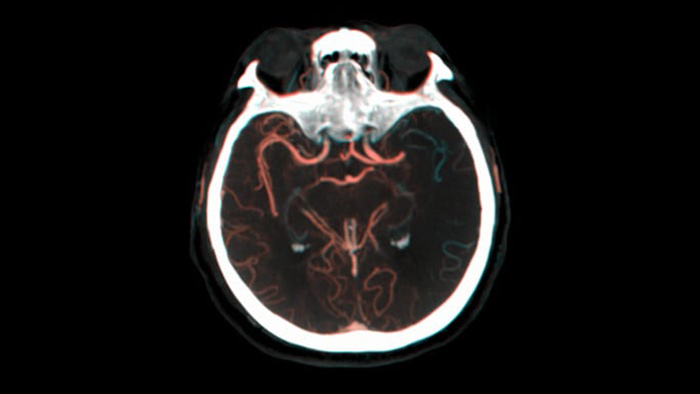

SmartCT Vaso IV

Enhance imaging of vessels and devices in the brain

SmartCT Vaso provides high resolution 3D imaging that reveals key information about cerebral vascular structures to support the highest possible spatial assessment of vessels in the soft tissue context.

See collateral filling

Visualization of collateral filling

Dual View for viewing early and late phase Cone Beam CT volumes side by side enhances identification of penumbra and enables visualization of collateral filling.